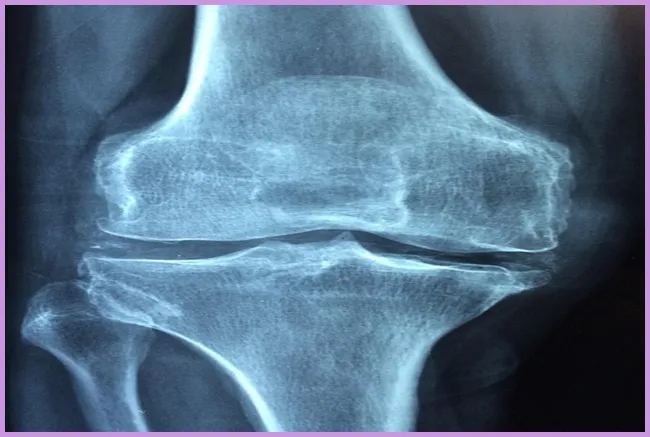

류마티스 관절염은 면역 시스템이 자신의 관절을 공격하여 염증을 발생시키는 자가면역 질환입니다. 이는 지속적인 통증과 불편함을 유발하며, 관절의 기능을 저하시킬 수 있습니다. 초기 단계에서는 일반적인 증상으로 시작하여 시간이 지남에 따라 악화될 수 있습니다. 이 질환은 주로 손, 발, 무릎과 같은 관절에 영향을 미치는 경향이 있습니다. 그렇다면 이 질환의 초기 증상은 무엇일까요?

관절염의 초기 증상 중에서도 가장 눈에 띄는 것은 관절의 통증입니다. 이 통증은 아침에 더욱 심해지는 경향이 있으며, 예를 들어 아침에 일어나서 발가락의 통증으로 인해 걷기가 힘들어질 수 있습니다. 이러한 증상은 해당 관절의 염증에 의해 발생합니다. 초기 증상이 나타났다면 전문가와의 상담을 통해 조기에 대처하는 것이 매우 중요합니다.